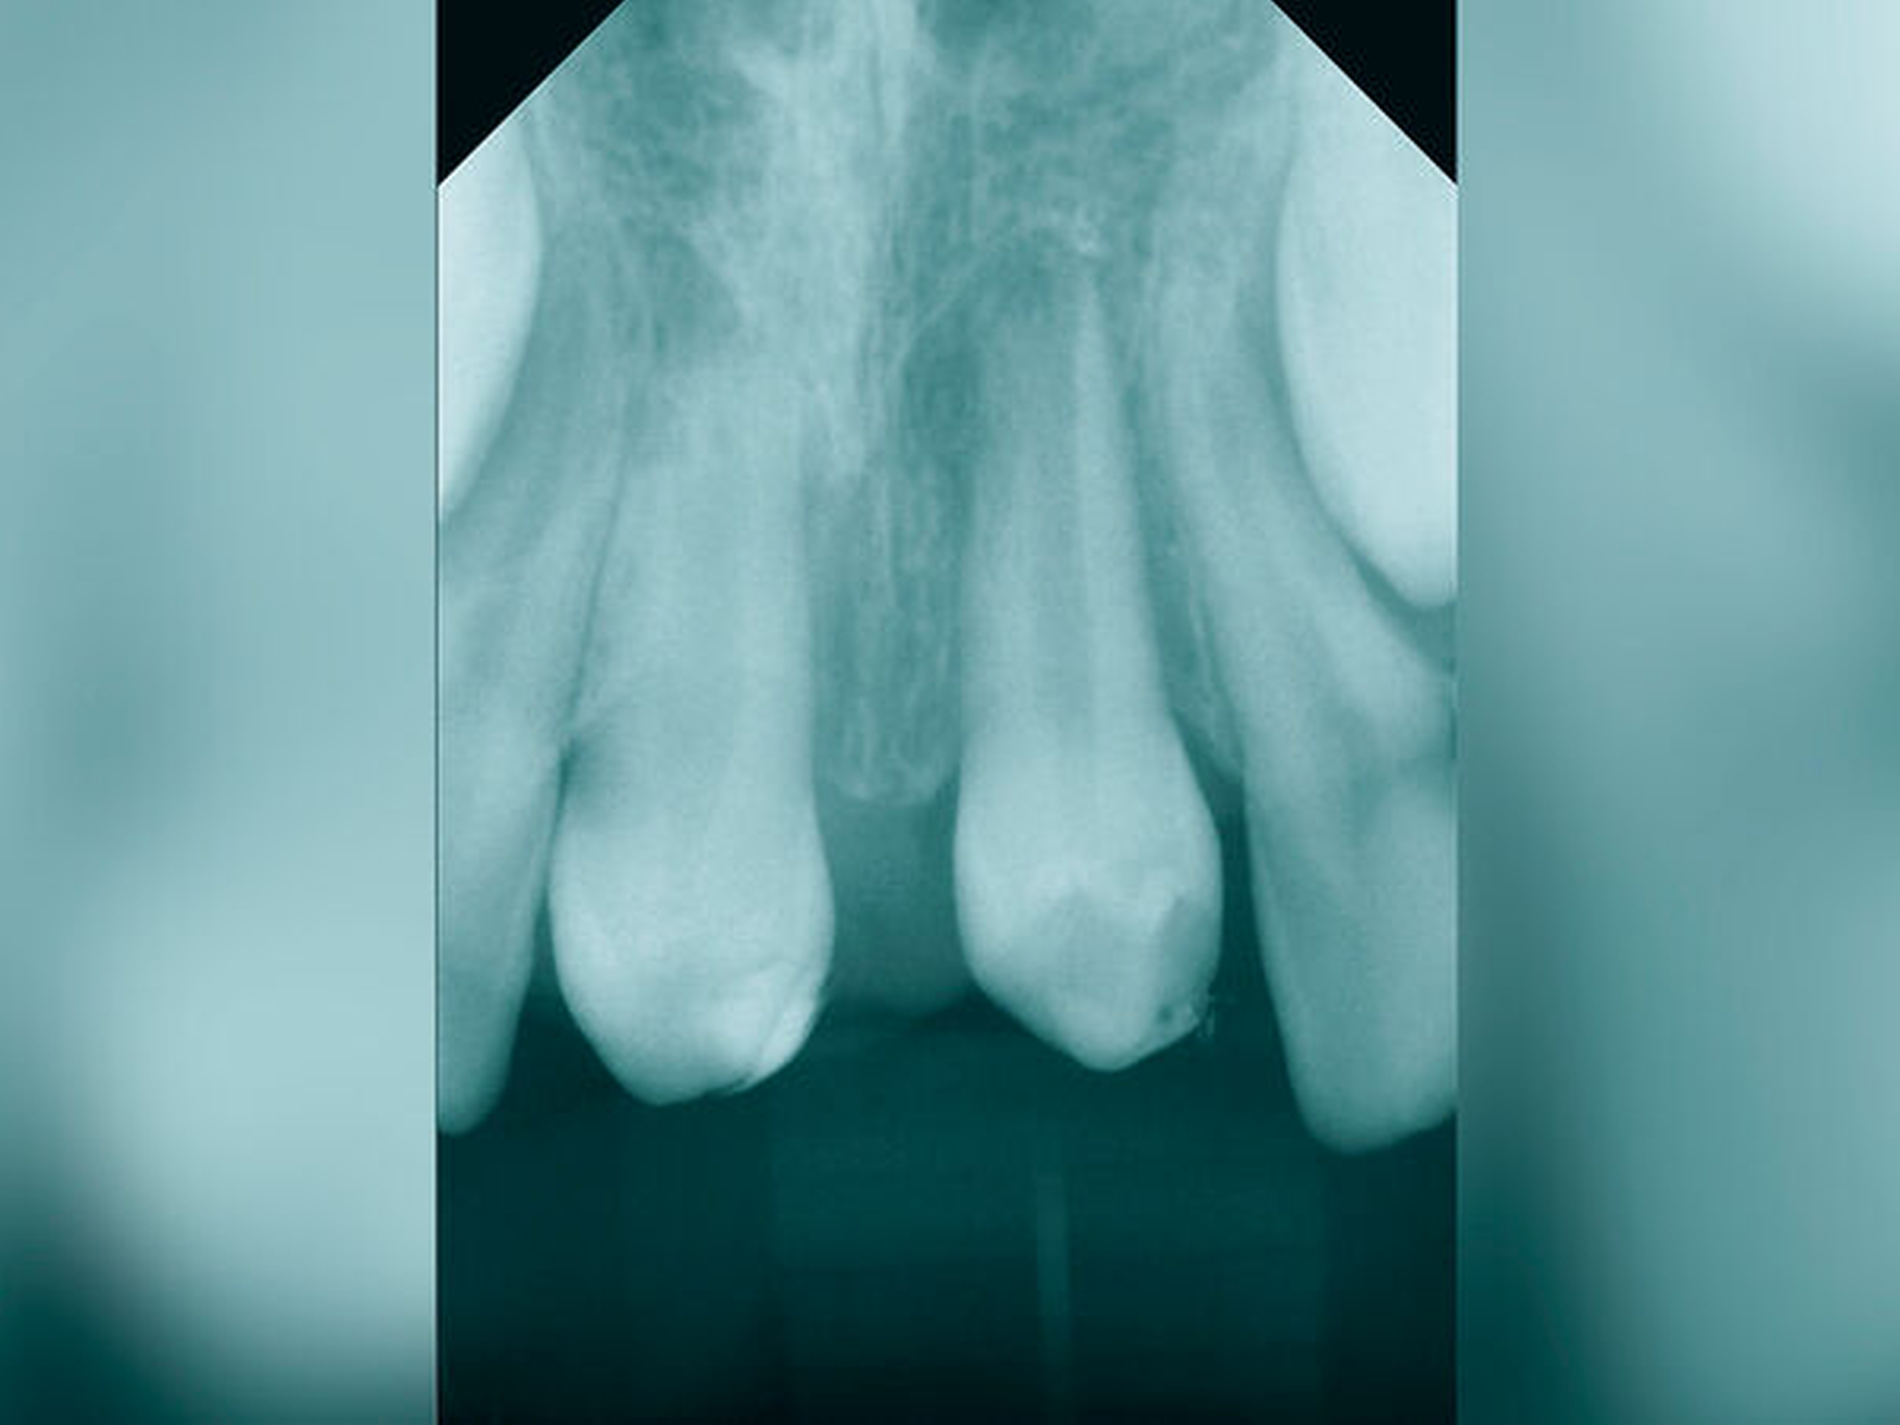

Die Häufigkeit für den Frontzahnverlust beträgt drei bis vier Prozent. Die Altersgipfel liegen zwischen dem achten und dem neunten sowie vom zwölften bis zum 14. Lebensjahr. Betroffene Zähne sind der mittlere und der seitliche Schneidezahn im Oberkiefer. Es besteht eine Korrelation der Häufigkeit zu den Zahnstellungsanomalien der vergrößerten sagittalen Schneidekantenstufe, dem schmalen Deckbiss mit protrudierten seitlichen Schneidezähnen und progen stehenden Einzelzähnen. Obwohl bei Avulsion die sofortige Reimplantation zum Erhalt des Zahnes führen kann, sind häufig Ankylosen des Parodonts und Wurzelresorptionen mit begrenzter Erhaltungswürdigkeit die Folgen. Eine fehlende Sensibilität, ein hoher Klopfschall und der röntgenologische Resorptionsnachweis sind diagnostische Anzeichen dafür.